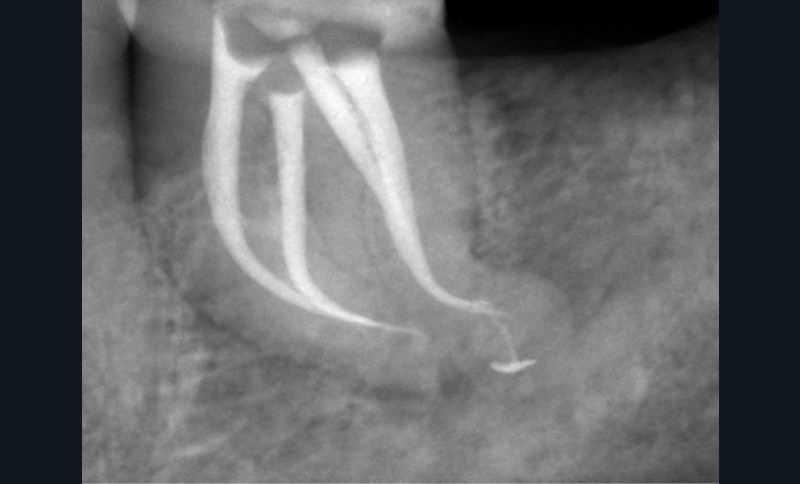

Le laser Erbium s’insère donc parfaitement dans nos principes actuels de traitements mini-invasifs comme activateur de nos solutions d’irrigation (fig. 1a à c).

Endal, en 2011, montrait également, en utilisant le micro CT Scanner, l’insuffisance de nettoyage des isthmes inter-canalaires à nos techniques conventionnelles [19]. L’utilisation du laser Er:YAG devenait alors incontournable dans le nettoyage de ces isthmes et des zones non instrumentées (fig. 2 et 3).